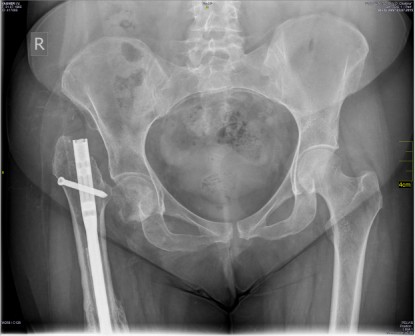

Пациентка В,30 лет. Травма 09.01.2014 в результате падения с высоты 5 этажа, в ЛПУ был поставлен диагноз: открытый перелом правого бедра и Th 11-12 позвонков. Пациентка госпитализирована в травматологическое отделение, за бугристость большеберцовой кости было наложено скелетное вытяжение в течение, выполнена ПХО раны с\3 правого бедра. Через 2 месяца после заживления раны бедра, скелетное вытяжение было снято, 04.03.2014 выполнена операция закрытого интрамедуллярного синтеза правого бедра. В апреле 2014 года была выписана на амбулаторное лечение, в мае 2014 начала ходить с частичной нагрузкой на правую ногу. 26 января 2015 года при повторной рентгенографии выявлен несросшийся перелом правой бедренной кости, была направлена в наш институт травматологии с диагнозом : Посттравматическая деформация правого бедра на фоне несросшегося перелома средней трети диафиза правого бедра после остеосинтеза интрамедуллярным стержнем. Псевдоартроз шейки правой бедренной кости, сопутствующие заболевания: Болезнь Иценко-Кушинга, ремиссия. Симптоматический сахарный диабет, инсулинопотребность. Диабетическая Нефропатия, ХПН0. Диабетическая сенсо-моторная полинейропатия нижних конечностей. Неправильно сросшиеся переломы тел ThXI-XII позвонков.

18.03.2015 Выполнен реостеосинтез правого бедра интрамедуллярным стержнем с антибактериальным покрытием со статическим блокированием. На 3-и сутки после операции пациентка была активизирована: начала ходить с помощью костылей с частичной нагрузкой на правую ногу. На повторном приеме через 3,5 месяца после операции установлен диагноз: сросшийся перелом правой бедренной кости после остеосинтеза интрамедуллярным стержнем, псевдоартроз шейки правой бедренной кости.

Можно ли предложить данной молодой пациентке что-то, кроме эндопротезирования т/б. И если вы думаете, что нет, то какая тактику будет дальше : вначале удалить стержень а потом выполнить эндопротезирование или выполнить их удаление стержня и протезирование в одну операционную сессию. Спасибо вам за ваши мнения !